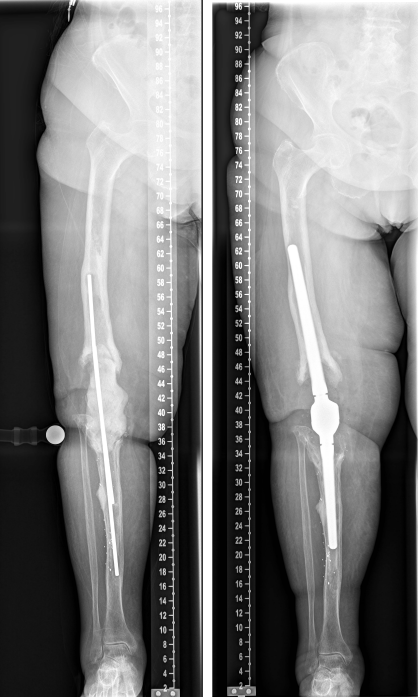

The duration of the surgical intervention was four hours and eight minutes. The patient was then mobilized with full weight bearing supervised by physiotherapists at ward level, which she tolerated well. The pain was significantly relieved during the hospital stay. The postoperative radiographs showed correct implant position and a satisfactory surgical result (Figure 9 [Fig. 9]). Microbiological and histological samples obtained intraoperatively showed no evidence of infection. Yet, the patient presented postoperatively with complete loss of active dorsiflexion of the ipsilateral foot. Neurological consultation and investigation confirmed the diagnosis of peroneal lesion. The patient was supplied by orthopedic shoes and orthesis. Further, electrotherapy was carried out.

Figure 9: The postoperative radiographs showed correct implant position and a satisfactory surgical result.

On one-year follow-up, the patient did not complain of any pain. The radiological findings one year after surgery showed no sign of loosening or any other pathological findings (Figure 10 [Fig. 10]). The neurological lesion has completely recovered. The Harris Hip Score HHS improved from 24 (prior to implantation of the arthrodesis) to 75 on one-year follow-up, the Western Ontario and McMaster Universities Osteoarthritis Index WOMAC improved from 86 to 20. The range of motion of the right hip joint one year after surgery was: extension/flexion 0/0/100°, abduction/adduction 30/0/20°, external rotation/internal rotation 30/0/20°.

Figure 10: The radiological findings one year after surgery show no sign of loosening or any other pathological findings.